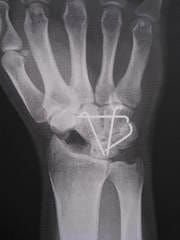

写真の固定してある骨がくっついて1個の骨になると最終的に成功だそうです。

壊れた骨は除去されたので今は穴が開いています。